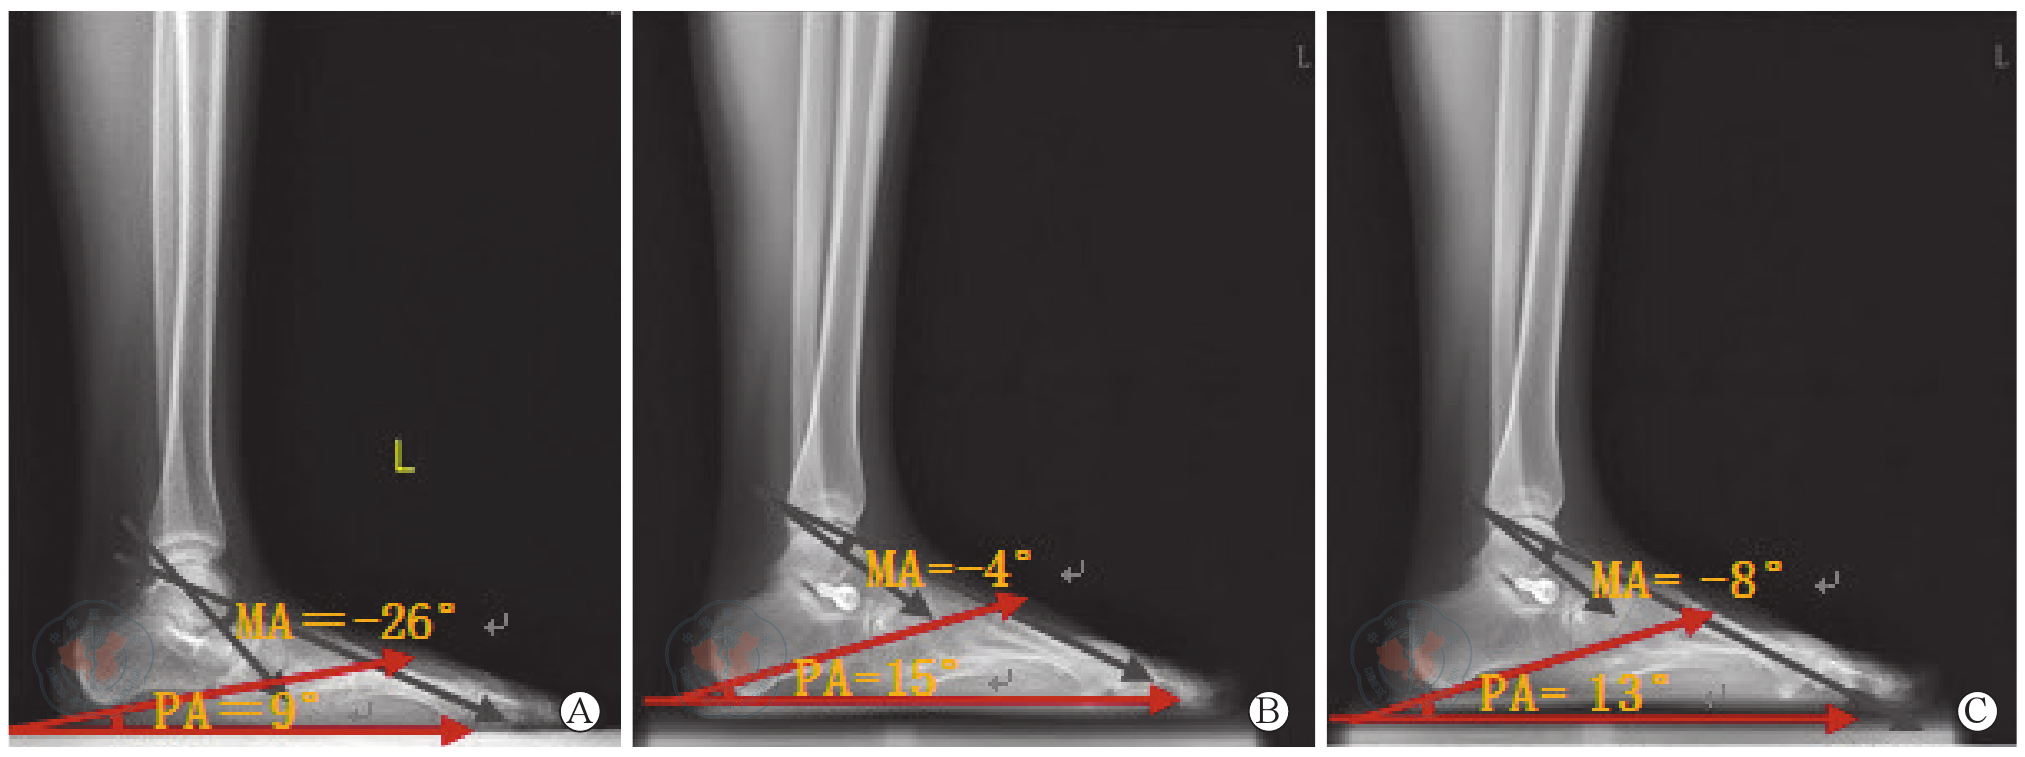

图1 跗骨窦螺钉内固定术前后左足负重侧位X线片,示矫正前后角度变化。图A为术前X线片;图B为术后X线片;图C为术后3个月X线片注:MA-Meary角(第一跖骨角);PA- Pitch角(跟骨倾斜角)

Figure 1 X-ray images at lateral view of left foot at weight-bearing position before and after tarsal sinus screw internal fixation, showing the changes of angels before and after correction. A is the image before surgery; B is the image after surgery; C is the image three months after surgeryNote: MA-Meary angle; PA-Pitch angle